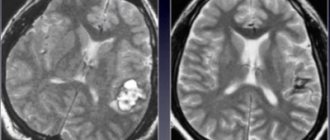

Диагностировать глиому мозга у взрослого или ребёнка можно только при помощи инструментальных процедур, основу которых составляет МРТ. Примечательно то, что лабораторные исследования практически не используются.

На начальных этапах заболевания глиома хиазмы и других отделов диагностируется крайне редко, и происходит это случайно. Первая степень почти никак себя не проявляет. Обнаруживается при компьютерной или магнитно-резонансной томографии.

Для оценки заболевания пациент направляется на магнитно-резонансную томографию, которая в полной мере показывает локализацию и особенности поражения мозга. Также больному могут назначить позитронно-эмиссионную томографию, эхоэнцефалографию и другие процедуры.

Перечисленные методы помогают с точностью визуализировать процесс, но определение вида и степени злокачественности не обходится без проведения микроскопического исследования. Анализ тканей возможен при получении их во время операции или путем биопсии.